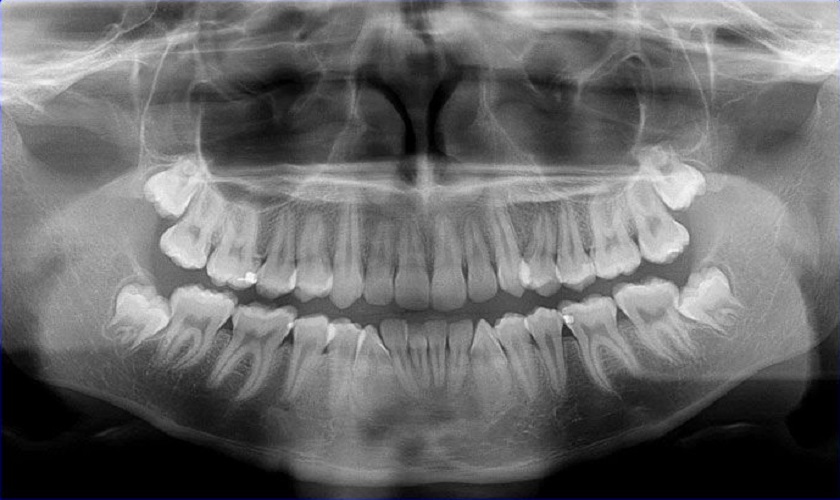

Chụp CT răng là phương pháp dùng tia X phản chiếu qua một tấm phim. Khi chụp, thiết bị chứa tia X đưa qua vùng hàm mặt của khách hàng sẽ được xử lý bằng điện toán bởi hệ thống cảm biến để đưa ra hình ảnh 3 chiều sắc nét. Nhờ vậy, các bác sĩ có thể quan sát dễ dàng và đưa ra chẩn đoán chính xác về các vấn đề răng miệng của khách hàng.

Kết quả chụp CT răng hỗ trợ rất nhiều cho bác sĩ trong việc chẩn đoán